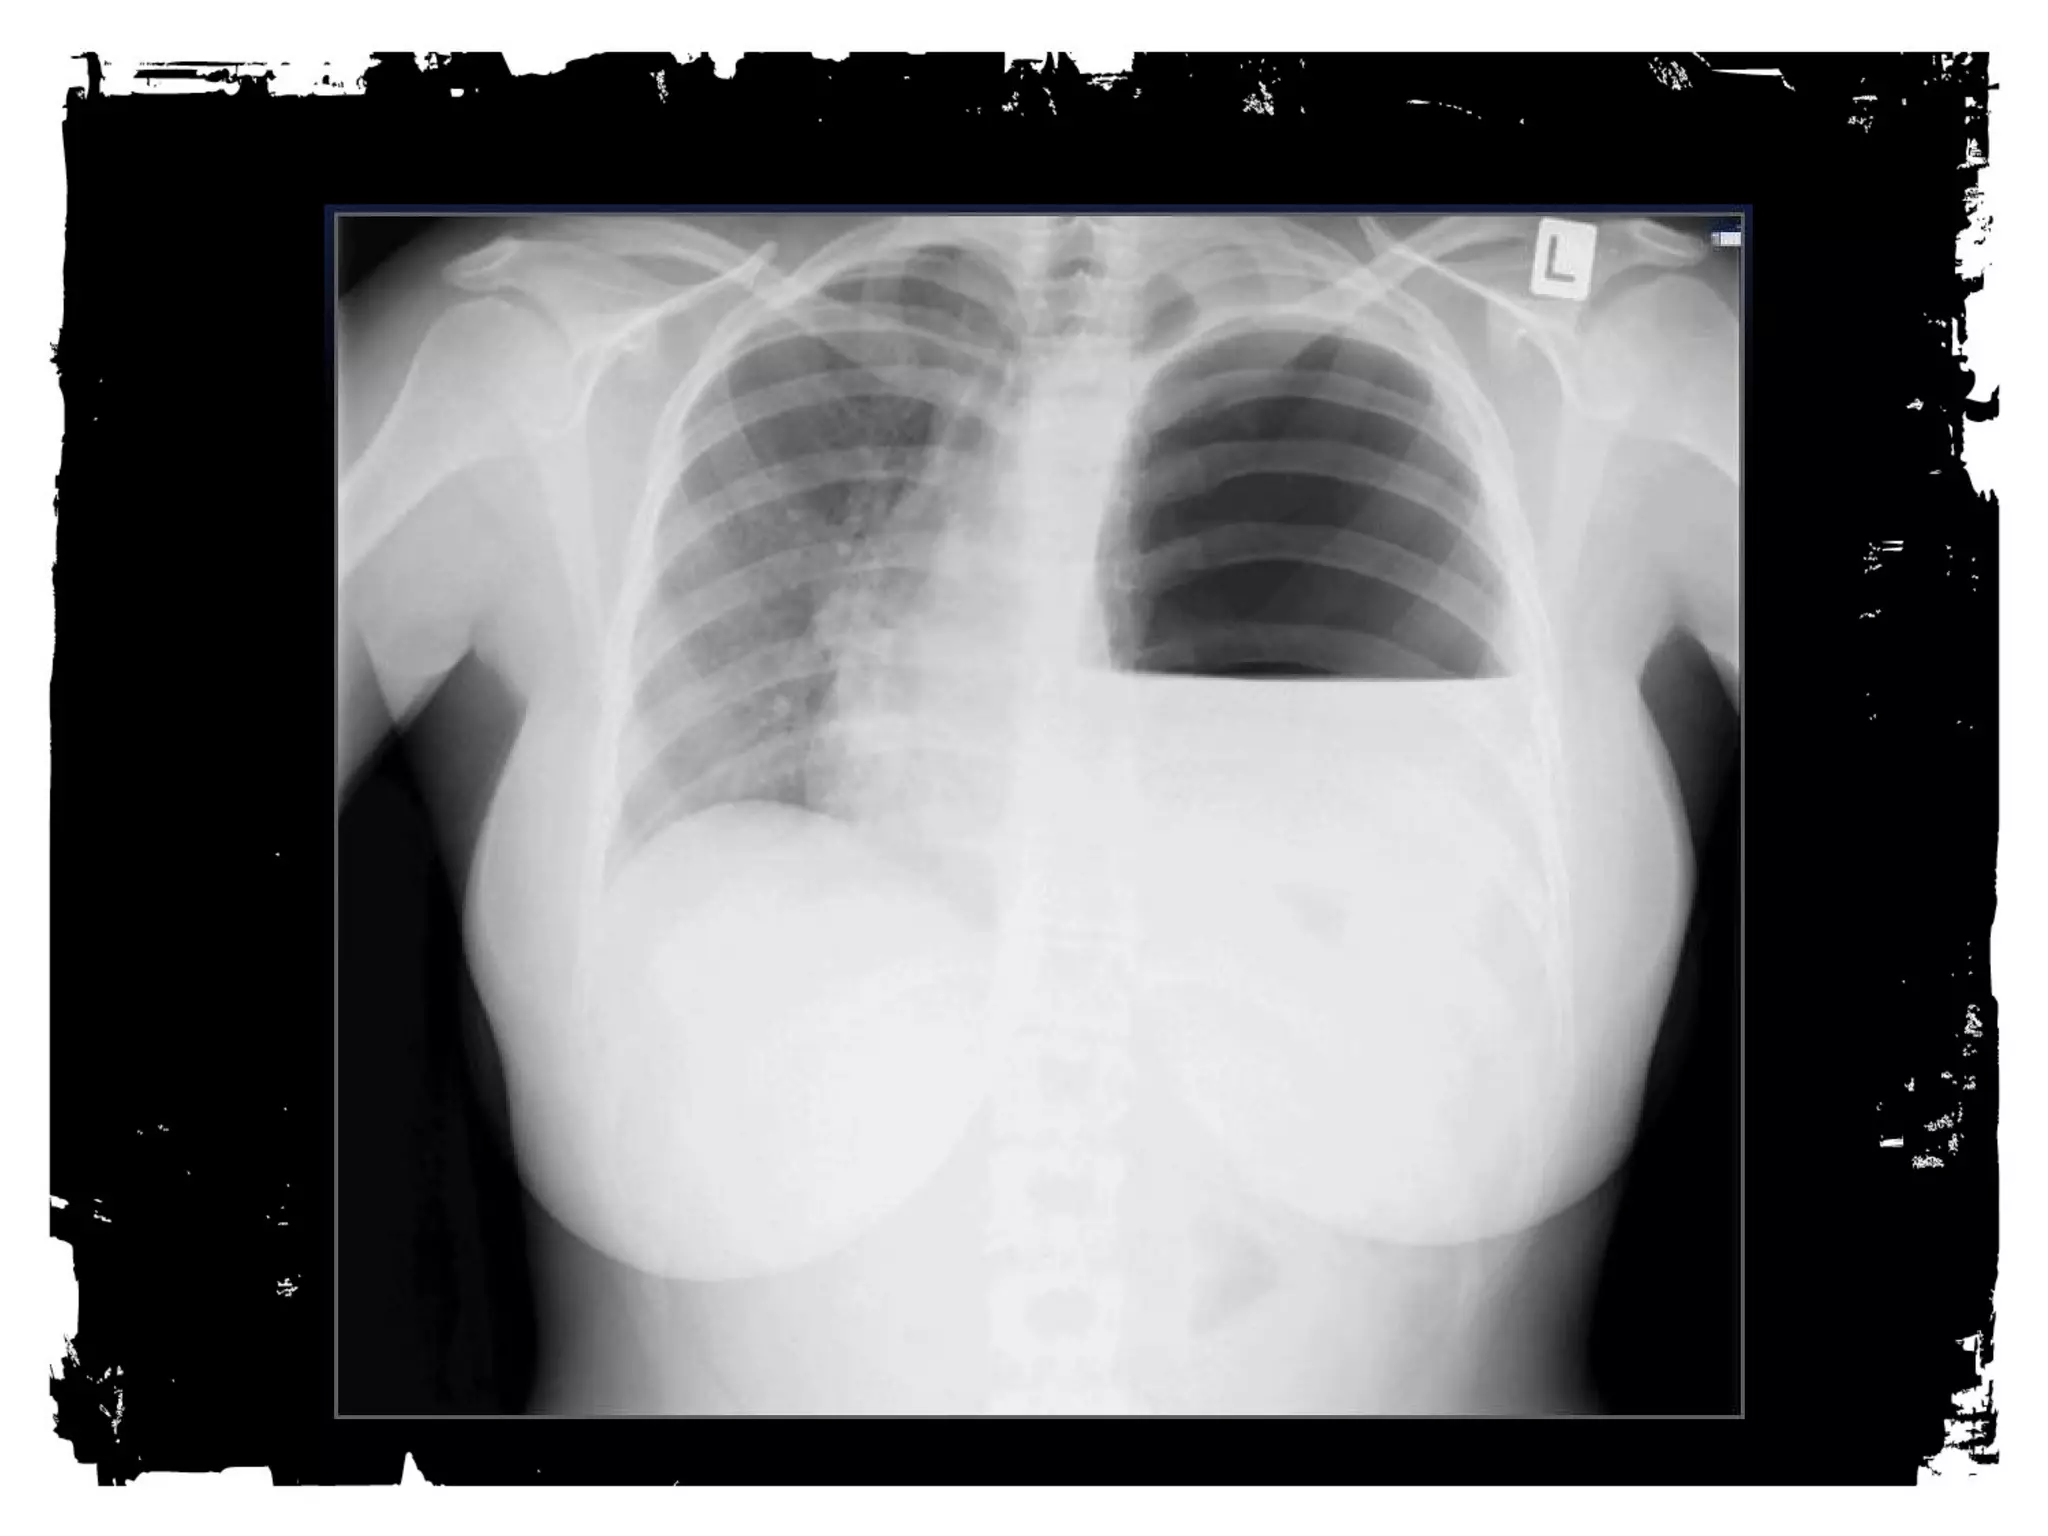

PNEUMOTHORAX

• Simple

• Tension

• Open

Pneumothorax: Simple

• Erect AP/PA view best

• Visceral pleural line

• No vessels or markings

• Variable degree of lung

collapse

• No shift

PNEUMOTHORAX: Tension

• Erect AP/PA view best.

• Shift of mediastinum away

from PTX side.

• Depressed hemidiaphragm.

• Degree of lung collapse is

variable.

HEMOTHORAX

• Venous or arterial bleeding

• 60% controlled by chest tube,

40% need operative

management

• Can miss hundreds of cc’s on

supine film

• Can be tension